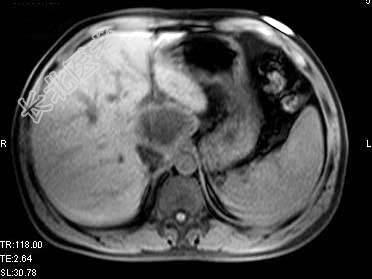

单项选择题根据所提供的图像,最可能的诊断是 ( )

A、肝囊肿

B、胆管细胞癌

C、先天性胆管扩张

D、肝脓肿

E、以上都不是